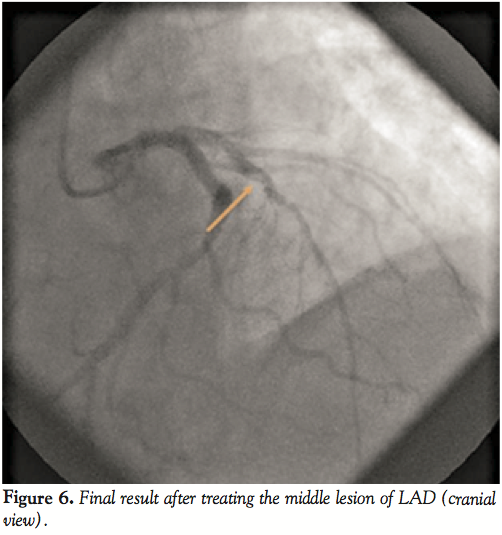

Ad hoc percutaneous coronary intervention (PCI) was performed maintaining the right radial approach. A 6 French (Fr) JL 3.5 guiding catheter (Cordis Europa NV) was chosen. The LAD lesions were crossed with a Pilot 50 guidewire (Abbott Vascular). The LAD paraostial lesion was predilated with a Sprinter 2 x 10 mm balloon (Medtronic) and an Endeavor Resolute 4 x 18 mm stent (Medtronic) was successfully implanted at 16 atm (Figure 4). Better visualization of the mid-LAD lesion was achieved and permitted direct implantation of a Nobori 3 x 14 mm stent (Terumo) at 16 atm to achieve an excellent angiographic result (Figure 5). The patient had no troponin elevation post-procedure and was discharged uneventfully after 2 days. One month later he reported symptomatic improvement (no effort dyspnea) and his ejection fraction increased from 35% to 45%. Six months after the procedure he was completely asymptomatic.